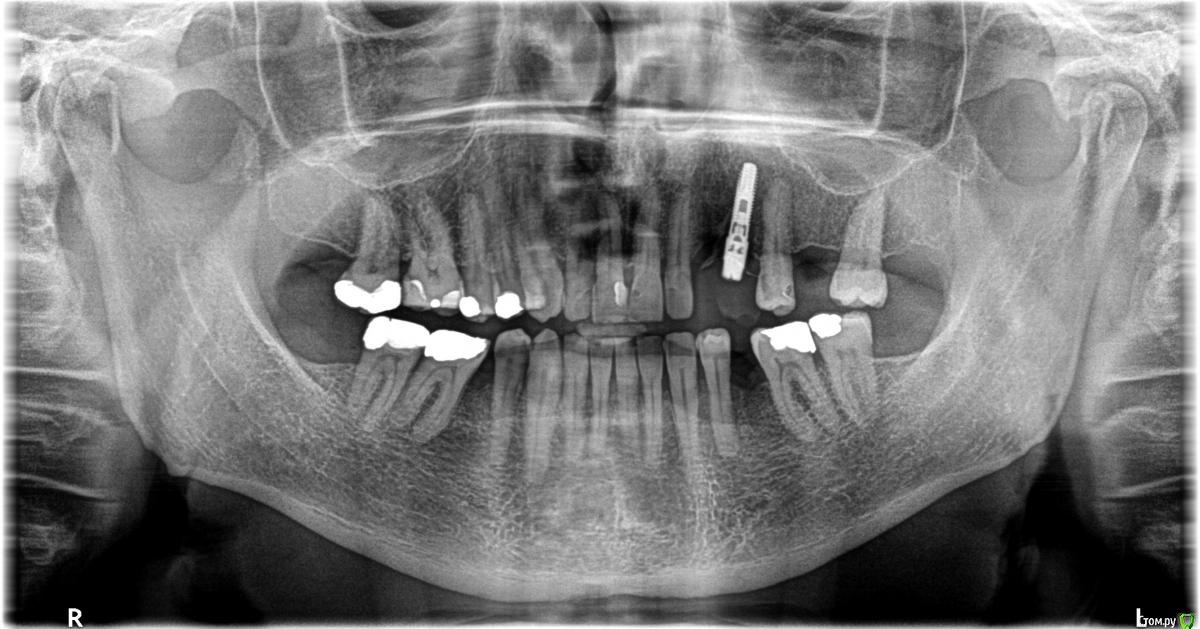

Mark4 Опубликовано 25 августа, 2017 Поделиться Опубликовано 25 августа, 2017 Всем доброго времени суток!Есть одна старая проблема, которой по времени уже стукнуло 17 лет. Относится она к протезированиюили имплантологии точно сказать не могу, но lдумаю, скорее к протезированию. 2000 году поставили в верхнем рядуна месте отсутствующих слева 3 и 4 зуба имплант /Semados /. Имплант был установлен не совсем перпедикулярно, нохирург сказал, что протезист подкорректирует. Протезист и подкорректировал, поставил один гигантскую коронку / зуб вампира /, но дырку закрыл. Эстетика , честно говоря, меня мало интересовала и все бы ничего, но вскоре пошли проблемы. При нагрузке, надавливании на коронку начинались ноющие болиотдававшиися в голове. Они то появлялись, то пропадали. И как-то подсознательно я простоперестал есть на левую сторону, стараясь избегать нагрузки на коронку. Но время шло, правая сторона усиленно изнашивалась и встал вопрос о решении проблемы с болями. Считая,что проблема связана с неправильным протезированием, обратился о замене коронки,она кстати была пластмассовая на металкерамику. Стоматолог, которая взялась за работу,сказала, что проблем не будет. Но все оказалось иначе. Разрезав коронку и выкрутивабатмент, она обнаружила под ним еще одно «устройство», которое для нее оказалось полнойнеожиданностью и которое она выкрутить так и не смогла. После титанических усилий по выкручиванию, единственное что она могла произнести – обратиться туда где ставили. Приятного было мало. И пришлось мне обратно обращаться к протезисту, который это ставил. После манипуляций с выкручиванием сильно болела голова и единственное на что хватало сил – сказать восстанавливаем тот статус-кво, который был. Что и было сделано. Прошло время и появились вопросы и поводу болей и по поводу «устройства?»Стоматолог, которая пыталась выкрутить «устройствро» уверяла, что его не должно бытьи нет ни в одном каталоге. По после отповеди протезиста, /а он у нас личность весьма и весьмаавторитетная / тихо смолкла. Удлинитель, так его назвал протезист, был установлен, чтоб приподнять абатмент. Был показан и каталог Semadosa – где оно имелось в наличии.А вот насчет ноющих болей внятного ответа я не получил ни от кого. Я обращалсяк нескольким стоматологам. Был внимательно рассмотрен соседний зуб. Паротондозныеболи. Один стоматолог выдвинул версию, что « удлинитель» + абатмент и один имплант на два зуба приводит к эффекту рычага и повышенной нагрзке т.д. Но после узнавании фамилиипротезиста все резко смолкают, смотрят на рентген и говорят, что на нем все нормально.Но болит то не рентген. Просто заговор какой-то. Хотелось бы узнать мнение врачей форумаи был бы признателен за любые мнения по поводу ноющих болей. Кто-нибудь в своейпрактике сталкивался с подобным? И насчет удлинителя / приподнимание абатмента /- где-то практикуется? Может ли нарушении техники имплантирования приводить к подобным болям? Если кто-то из пациентов сталкивался с чем-то подобным, тоже милости просим Ссылка на комментарий

red_butler Опубликовано 28 августа, 2017 Поделиться Опубликовано 28 августа, 2017 А когда сделан этот снимок? Ссылка на комментарий

Mark4 Опубликовано 28 августа, 2017 Автор Поделиться Опубликовано 28 августа, 2017 23 августа сего года. Ссылка на комментарий